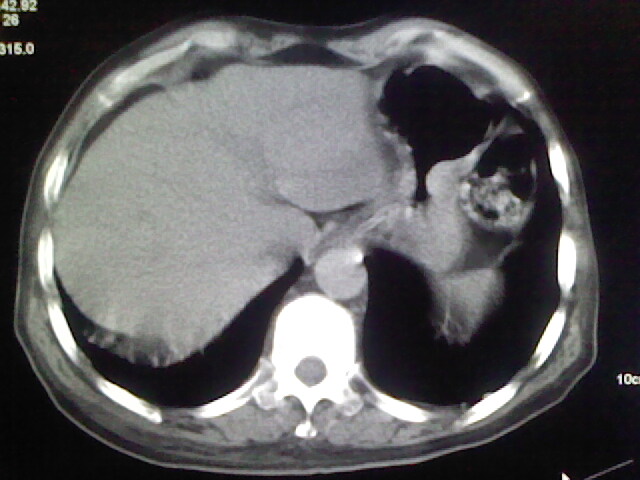

男,70岁,脑出血,长期卧床,左侧背部可触及肿块

慢性间质性炎症,与老年患者长期卧床相关,胸壁软组织及肋骨未见异常。

肺部感染,背部筋膜增厚,考虑坠积性水肿或炎症